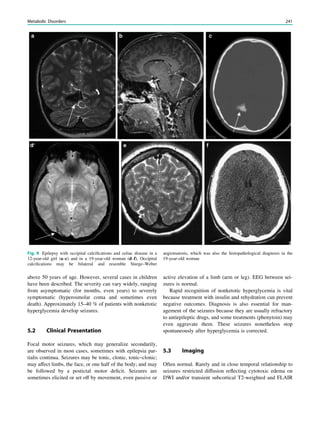

1 Introduction.......................................................................... 29

2 Theoretical Considerations................................................. 29

3 Clinical Practice................................................................... 30

4 Requirements for MR Quality........................................... 32

4.1 Orientation ............................................................................. 32

4.2 Spatial Resolution.................................................................. 32